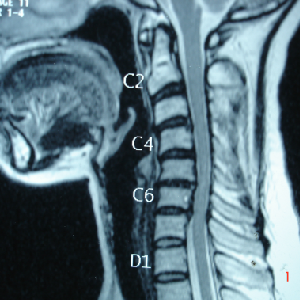

Generally cervical myelopathy with kyphotic cervical slpine is treated with anterior

decompression and fusion.

A very young pt of 25 years old, belonging to very good family, an engineer, had

tuberculosis of cervical

spine with destruction of C7 vertebra

if he would not get urgent attention and surgery, he could have landed up in developing

paraplegia

he was operated from front of the neck, a new vertebra(tricortical bone graft) was

put and fixed with plate

Cervical Laminoplasty